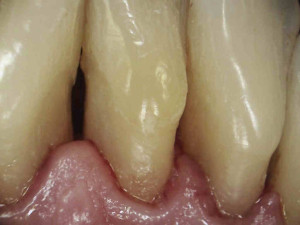

Naszym celem jednak jest nie tylko ładny wygląd zębów ale wyleczenie stanu zapalnego dziąseł, a to nie będzie możliwe bez dokładnego wyedukowania pacjenta. Higienistka przeprowadziła szczegółowy instruktarz prawidłowej metody szczotkowania – pokaz na modelu i samodzielna próba pacjenta na własnych zębach. Pacjent nauczył się również stosowania szczoteczek międzyzębowych, będących w jego przypadku niezbędnym akcesorium higienicznym ze wglądu na szerokie przestrzenie miedzyzębowe. Zalecone zostały środki pomocnicze – Eludril do płukania, pasta Elgydium Anti-Pacjent spotkał się z nasza higienistka jeszcze dwa razy, w celu dokonania kontroli i ewentualnego doczyszczenia. Na drugiej wizycie kontrolnej dziąsła pacjenta wyglądały tak: zdjęcie 3, zdjęcie 6. Komentarz jest chyba zbędny: różnica widoczna gołym okiem, dziąsła są zdrowe, bladoróżowe, bez opuchlizny. Gratulujemy!!!